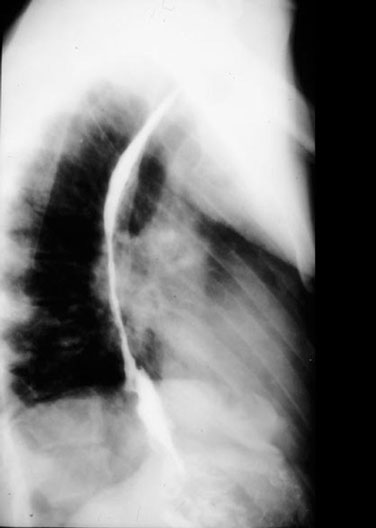

Esophagus

1. Esophagus

2. Diaphragm

3. Cardiac part of stomach